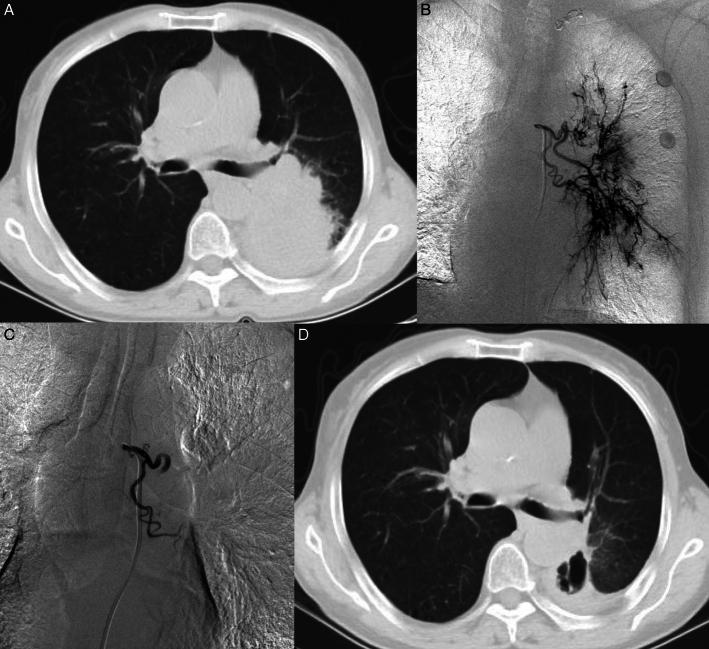

Background: Bronchial arterial chemoembolization (BACE), as a safe and effective minimally invasive treatment method, is increasingly being accepted by more and more patients with advanced nonsmall-cell lung cancer (NSCLC). In recent years, drug-eluting beads (DEB)-BACE has also been applied in the field of lung cancer. It is still unclear which is more recommended due to the limited number of comparative studies between conventional BACE (C-BACE) and DEB-BACE.

Purpose: To compare the safety and efficacy of C-BACE (BACE with gelfoam particles) and DEB-BACE for advanced NSCLC.

Materials and methods: From January 2021 to April 2023, 48 consecutive patients (37 males and 11 females) with advanced NSCLC treated with DEB-BACE (group A) or C-BACE (group B) at our center were collected retrospectively in this study. There were 18 patients in group A and 30 patients in group B. The technical success rate, adverse events, objective response rate (ORR), disease control rate (DCR), progression-free survival (PFS), and overall survival (OS) were compared between the 2 groups.

Results: The technical success rate in both groups was 100%. The median OS times were 19.5 months and 12.5 months in group A and group B, respectively ( P =0.0062). The median PFS times were 13 months and 7 months in group A and group B, respectively ( P =0.0072). The ORRs at 6 months were 72.2% and 46.7% in group A and group B, respectively ( P =0.084). The DCRs at 6 months were 88.9% and 63.3% in group A and group B, respectively ( P =0.043). Grade 1 adverse events like chest pain, and cough were common, while serious adverse events did not occur.

Conclusions: BACE with DEB or gelfoam particles were equally safe. The DEB-BACE showed better survival and tumor response than C-BACE for advanced NSCLC.